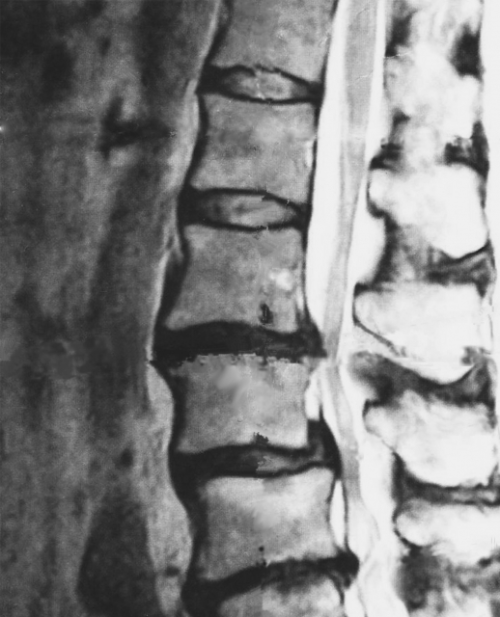

むち打ち症

「頸部捻挫」「頸部挫傷」「外傷性頸部症候群」で表記されます。

むち打ち症は、交通事故の追突時に日常生活では加わらない力が筋肉に加わる事で、耐え切れずに損傷を受ける事で生じる障害です。

首の部分、背中の部分、腰の部分の筋肉、関節が損傷してる状態です。